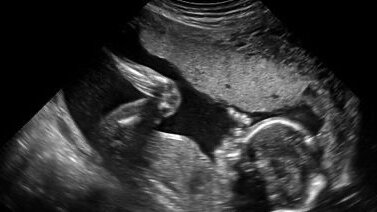

Патология плода в I триместре: асцит(жидкость в брюшной полости), мегацистис(увеличеный мочевой пузырь), омфалоцеле.